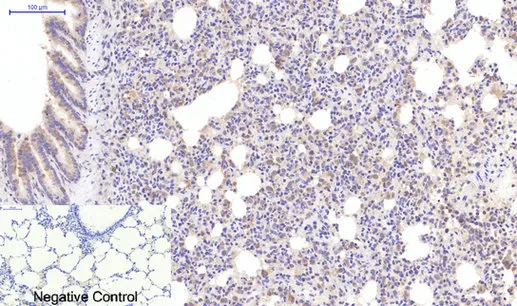

NSE(13E2)Mouse Monoclonal Antibody

Cat: AMM14910

Size1:50μL Price1:$118

Size2:100μL Price2:$220

Size3:200μL Price3:$380

Application:WB,IHC-P,IF-P,IF-F,ICC/IF

Reactivity:Human,Mouse,Rat

Conjugate:Unconjugated

Optional conjugates: Biotin, FITC (free of charge). See other 26 conjugates.

Gene Name:ENO2